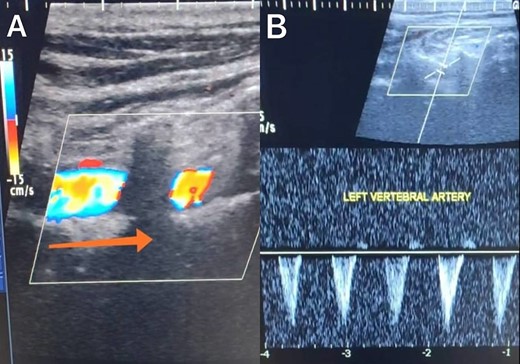

A 65-year-old male presented with recurrent transient ischemic attacks (TIAs), characterized by severe balance disturbances, transient alterations in consciousness, and visual obscurations. Clinical examination revealed high blood pressure in the right arm and absent left radial and brachial artery pulses. Vital signs were normal. Laboratory tests are analyzed as follows: urea: 22 mg/dl, glucose: 150 mg/dl, cholesterol: 199 mg/dl, and triglycerides: 222 mg/dl. A medical history of type 2 diabetes mellitus (DT2), hypertension (HTN), hyperlipidemia, ischemic heart disease, and a heavy smoking history were recorded. Five years before presentation, the patient underwent coronary stenting. Medication history included metformin 1000 mg, aspirin 81 mg, rosuvastatin 40 mg, and ramipril 5 mg. Neck duplex ultrasound (DU) showed normal flow direction and insignificant atherosclerotic plaques in the left internal carotid artery (CA) and left external CA (Figs 1 and 2), normal common CA (Fig. 3), a completely inverted flow direction in the left VA (Fig. 4) that suspected a significant ostial lesion in the left SCA. Multi-slice computed tomography angiography demonstrated 99% stenosis at the left SCA origin and confirmed the presence of SSS (Fig. 5). A balloon angioplasty was unsuccessfully attempted to expand the left SCA. A left carotid VA bypass surgery was performed, and a vascular graft was used to establish a blood flow pathway between the left VA and the left CA. By follow-up, the patient was stable without complications.

Duplex ultrasound showing a normal flow direction and insignifcant atherosclerotic plaques in the left internal carotid artery.